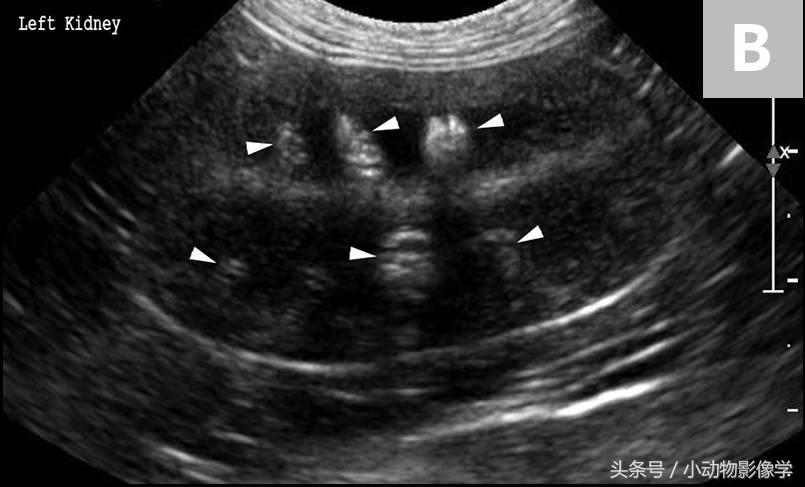

图5A、犬腹部侧位平片,可见腹膜后隙后方和肾脏背侧有两个界限清楚的椭圆形矿物化不透明重叠影像(箭头)。结合腹背位正片(这里没有显示),这些结石可能与右输尿管相关。

图5B、图5A中犬的超声图像,证实了矿物化结构位于右侧输尿管内。可见输尿管显著扩张(三角箭头之间),及输尿管腔内的两个结石引起的远端声影伪像(S)。